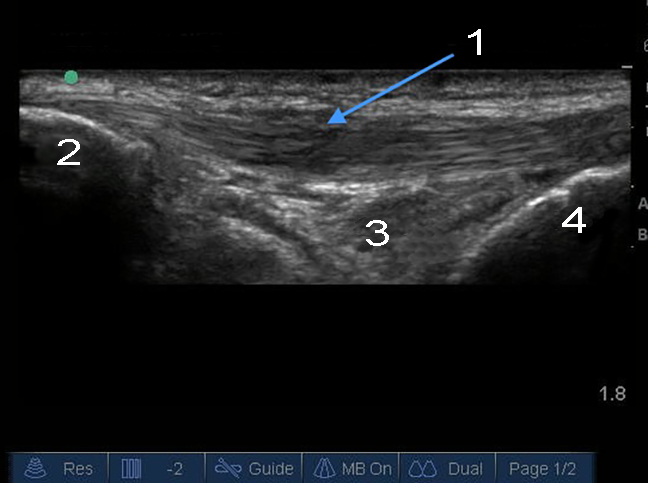

肥厚性膝蓋腱縦方向

膝蓋骨

Hoffa Fat Pad

脛骨